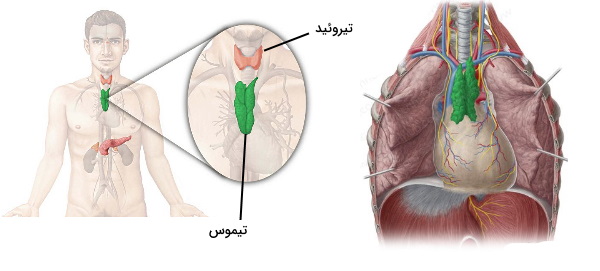

در بخشهای قبلی از این مطلب مجله فرادرس جایگاه استخوانها و ماهیچههای اسکلتی در آناتومی قفسه سینه را توضیح دادیم. غده تیموس، ریهها و قلب اندامهای داخلی قفسه سینه هستند که د راین بخش آناتومی آنها را توضیح میدهیم. غده تیموس یکی از اندامهای سیستم لنفاوی و محل تکامل لنفوسیتهای T است.

بخش اصلی غده تیموس در ناحیه بالایی مدیاستوم و پشت استخوان مانبوریوم قرار دارد. اما در بعضی از افراد این غده بالاتر و نزدیک تیروئید قرار میگیرد. این غده مسطح و نامتقارت از فولیکولهای زیادی تشکیل میشود که ساختار و عملکرد آنها متفاوت است. فولیکولهای قشری از سلولهای اپیتلیال و لنفوسیتهای T تشکیل شده است. تعدادد لنفوسیتهای T در فولیکولهای میانی کمتر و تعداد سلولهای اپیتلیال بیشتر است. «تودههای هاسال» (Hassall’s Corpuscles) در این بخش از تیموس قرار دارد. مطالعه مطلب تیموس چیست از مجله فرادرس اطلاعات بیشتری دو مورد فیزیولوژی این غده در اختیار شما قرار میدهد.